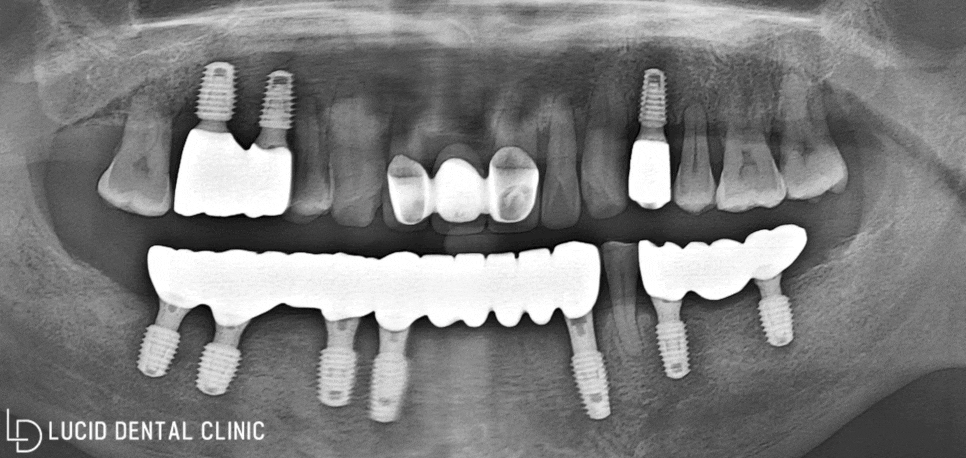

- 최종 종료

다음과 같이 위턱과 아래턱에

임플란트 수술 을 진행했습니다.

보다 높은 심미성을 기대하기 위해

지르코니아 재료로 제작하였는데요

주변 치아와 유사한 색조 및 형태를 통해

자연스럽게 어우러질 수 있도록 제작했습니다.